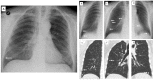

Objectives: To evaluate the capability of digital tomosynthesis (DTS) to characterize suspected pulmonary lesions in the so-called hidden areas at chest X-ray (CXR).

Materials and methods: Among 726 patients with suspected pulmonary lesions at CXR who underwent DTS, 353 patients (201 males, 152 females; age 71.5 ± 10.4 years) revealed suspected pulmonary lesions in the apical, hilar, retrocardiac, or paradiaphragmatic lung zones and were retrospectively included. Two readers analyzed CXR and DTS images and provided a confidence score: 1 or 2 = definitely or probably benign pulmonary or extra-pulmonary lesion, or pulmonary pseudo-lesion deserving no further diagnostic work-up; 3 = indeterminate lesion; 4 or 5 = probably or definitely pulmonary lesion deserving further diagnostic work-up by CT. The nature of DTS findings was proven by CT (n = 108) or CXR during follow-up (n = 245).

Results: In 62/353 patients the suspected lung lesions were located in the lung apex, in 92/353 in the hilar region, in 59/353 in the retrocardiac region, and in 140/353 in the paradiaphragmatic region. DTS correctly characterized the CXR findings as benign pulmonary or extrapulmonary lesion (score 1 or 2) in 43/62 patients (69%) in the lung apex region, in 56/92 (61%) in the pulmonary hilar region, in 40/59 (67%) in the retrocardiac region, and in 106/140 (76%) in the paradiaphragmatic region, while correctly recommending CT in the remaining cases due to the presence of true solid pulmonary lesion, with the exception of 22 false negative findings (60 false positive findings). DTS showed a significantly (p < 0.05) increased sensitivity, specificity, and overall diagnostic accuracy and area under ROC curve compared to CXR alone.

Conclusions: DTS allowed confirmation or exclusion of the presence of true pulmonary lesions in the hidden areas of the chest.